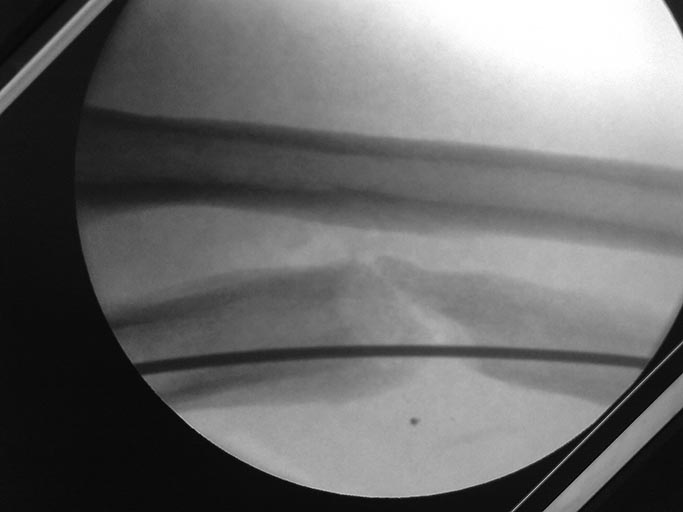

Вчера больной прооперирован - головку лучевой кости пришлось резцировать (сгибание было около 100 гр.и все бы ничего, но ось локтевой кости очень плохо выравнивалась ,сгибание после резекции увеличилось на 20 гр.) Снимок после резекции головки.

Головку использовали на аутопрансплантаты и попробовали поставить пластину.

А потом передумали, наложили два кольца, сделали остеотомию и интрамедуллярно армировали гвоздем, и начнем тянуть с 5х суток.